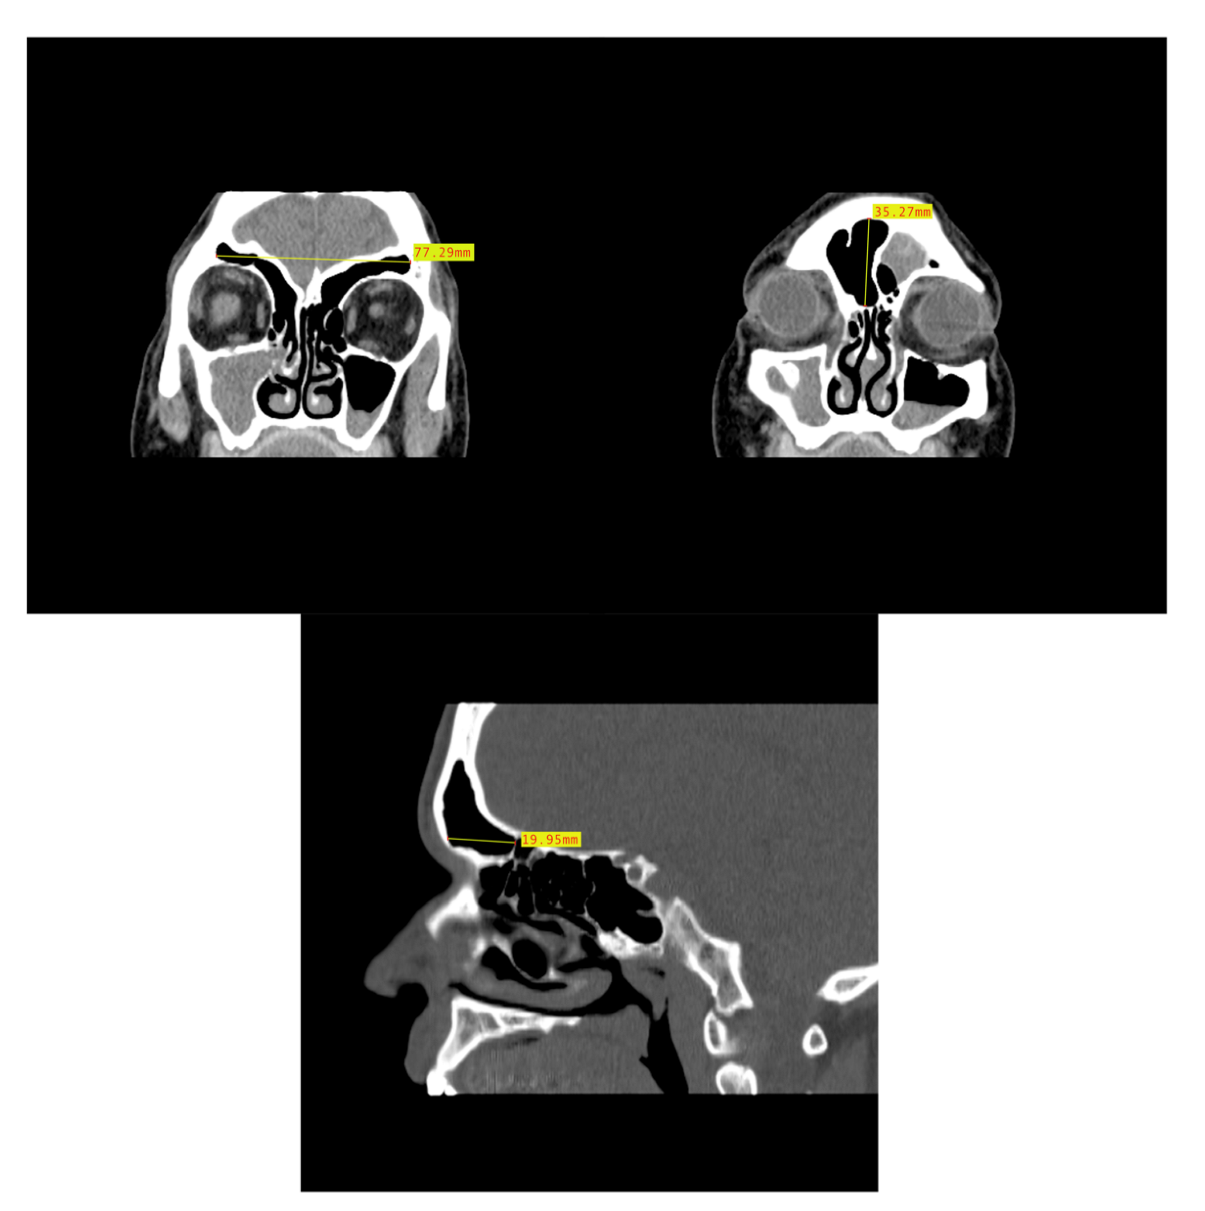

In order to assess the dimensional variation based on assigned sex and population affinity, the maximum heights, widths, and depths of each frontal sinus were examined individually and in combination. In order to capture the dimensions, the MicroDicom viewer was used because the Shape v1.3 software used in the morphological analysis lacks scaling capabilities. While viewing the images in the MicroDicom viewer, linear measurements in millimeters were obtained to the hundredths. The maximum height and maximum width of the frontal sinus were obtained from images in the coronal plane, while the maximum depth was taken from slices in the sagittal plane (Figure 5). Additionally, the product of height, width, and depth (H × W × D) was used as a rough proxy for volume; however, we acknowledge that this dimension does not accurately represent the contoured volume of sinuses. The measurements were recorded in a Microsoft Excel spreadsheet with the individual’s study ID number, assigned sex, and population affinity.

Figure 5.

Example of CT image slice showing the maximum height (left) and width (right) measurement of the frontal sinus in the coronal plane and the frontal sinus maximum depth (bottom) in the sagittal plane from three study individuals (yellow lines and red boxes).